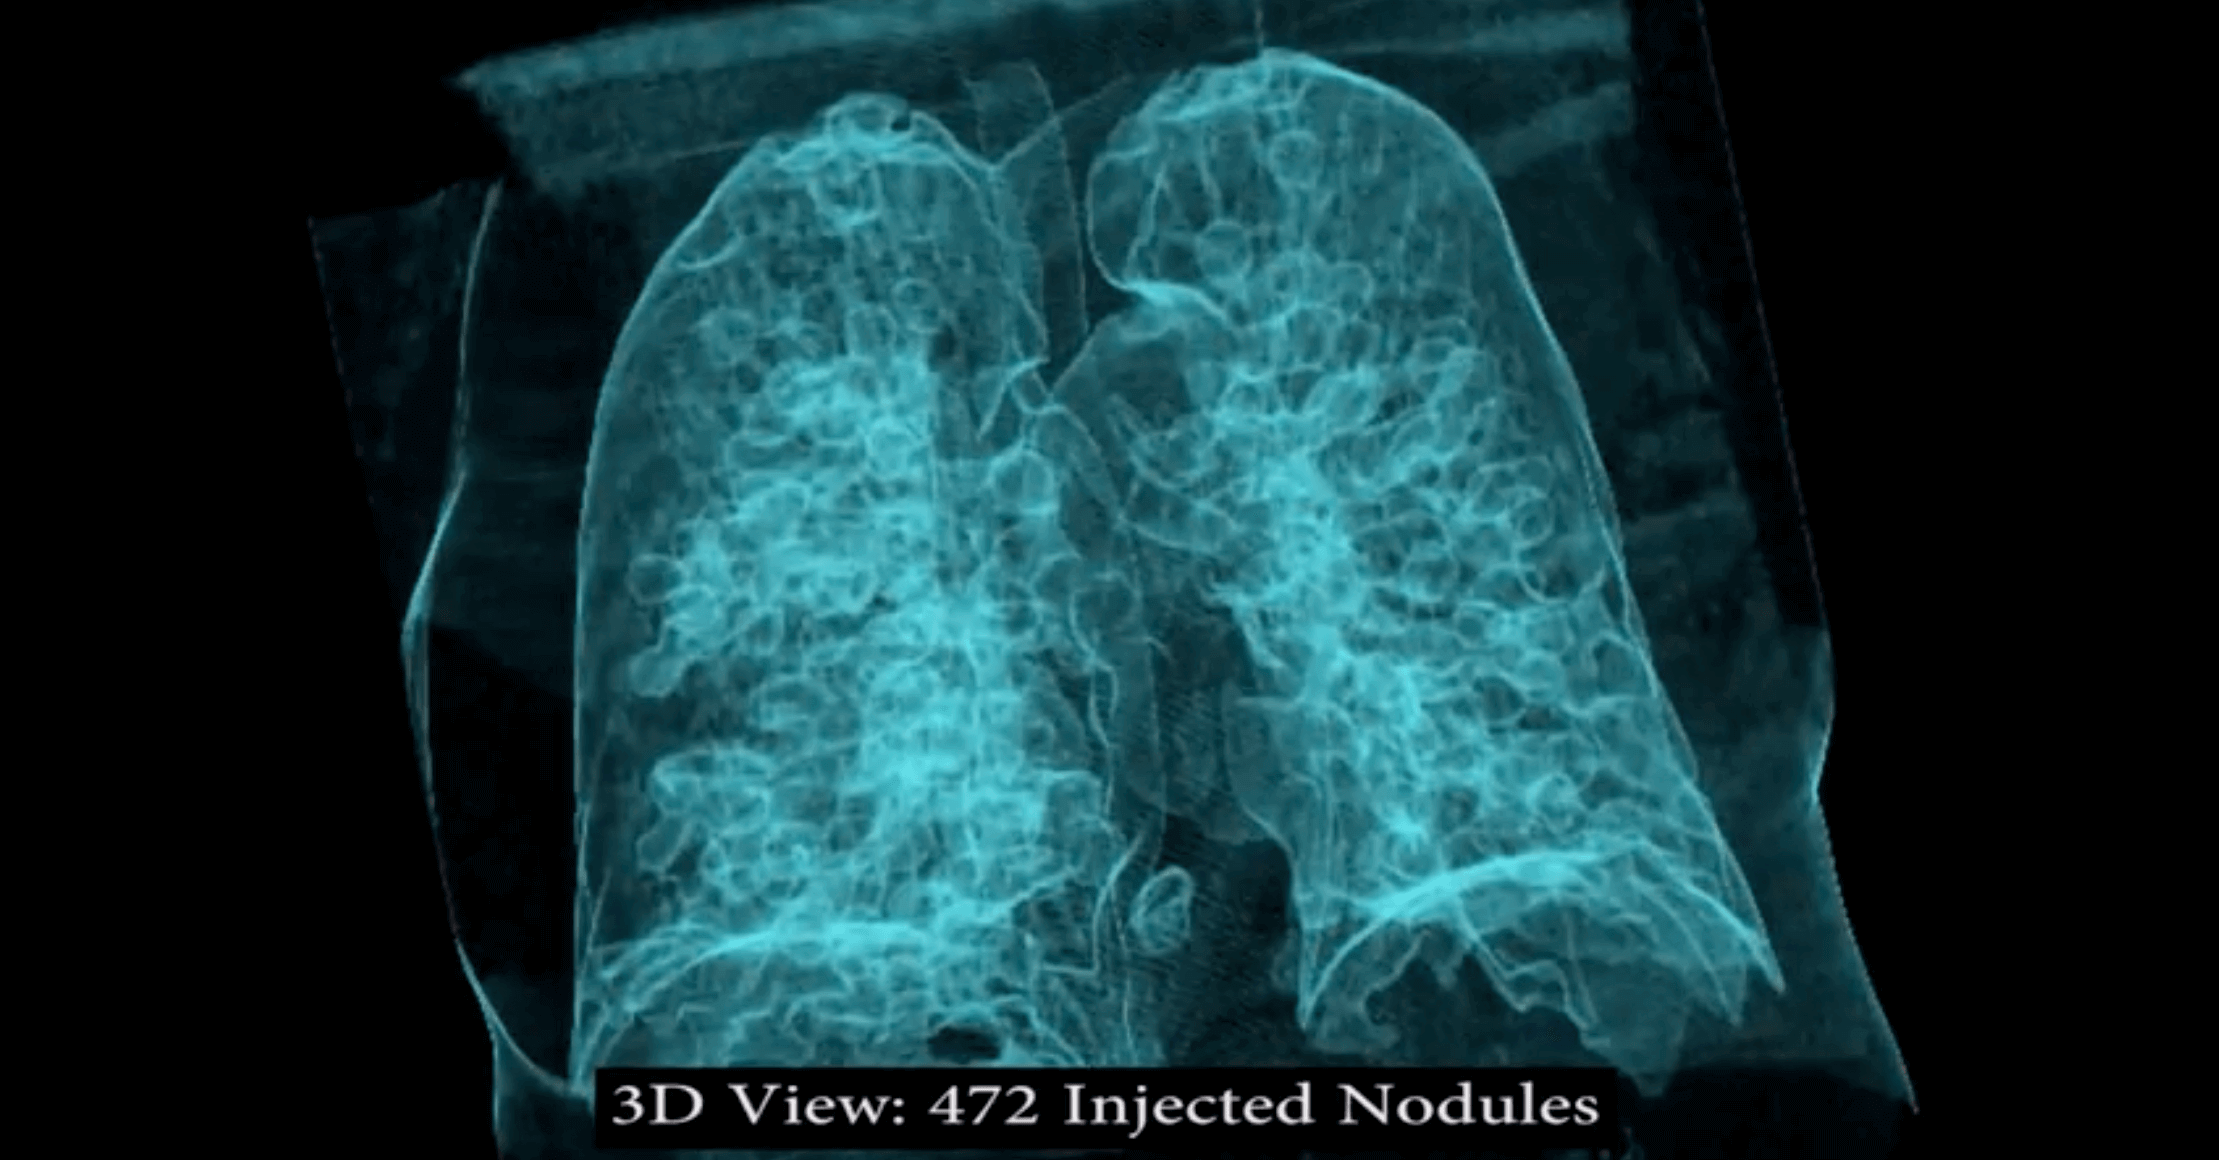

Israeli researchers created malware that can alter CT and MRI scans well enough to fool radiologists into misdiagnosis. The deep-learning software can create realistic looking fake malignant tumors or can hide real growths from scans in close to real time.

"We implement the attack using a 3D conditional GAN and show how the framework (CT-GAN) can be automated," said Yisroel Mirsky, Tom Mahler, Ilan Shelef, and Yuval Elovici in their study. "Although the body is complex and 3D medical scans are very large, CT-GAN achieves realistic results which can be executed in milliseconds. "

In a blind study, using 70 altered lung scans and three experienced radiologists, the software tricked them almost every time. In instances where they were looking at faked growths, they delivered a cancer diagnosis 99 percent of the time. In scans where the malware had removed actual tumors, the radiologist gave the all clear 94 percent of the time.

The researchers then ran tests against software designed to detect lung cancer in images, which radiologist use to confirm their own diagnosis. It misdiagnosed faked nodules 100 percent of the time.